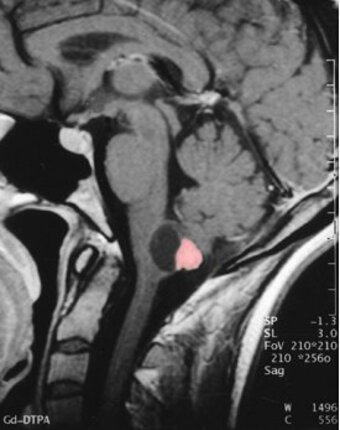

Hemangioblastomas of the central nervous system are benign tumors. They mostly occur in the posterior fossa or spinal cord. These tumors can develop sporadically or hereditarily as a manifestation of von Hippel-Lindau disease. Typically, the tumors develop an adjacent tumor-associated cyst as a small, solid formation along the wall of a large cyst. These cysts contain an amber-colored liquid and in some cases form a so-called syrinx in the spinal cord.

What is the medical treatment?

In general, the tumors grow slowly so that an annual check-up is sufficient. For the primary diagnosis and follow-up examination, an MRI with contrast is the method of choice. If treatment is necessary, the tumor is removed microsurgically. Since hemangioblastomas are benign tumors, the tumors can usually be completely removed and generally do not recur. Radiation therapy has so far provided no convincing evidence of success. Drug therapy methods are currently the subject of scientific investigation. There is currently no drug that has been shown to be effective against hemangioblastomas.